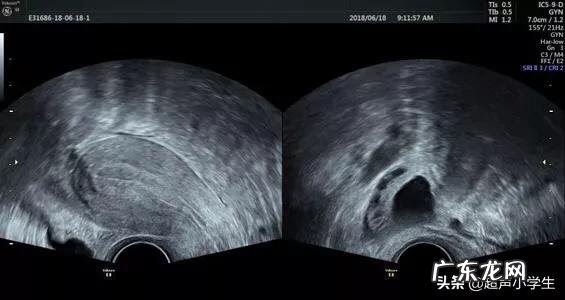

一、超声监测法

超声检查监测法主要是用于备孕的女性 。超声检查时最直观而且准确的检查方法,就是利用超声技术直径看到有无优势卵泡,一般观察到有优势卵泡,那么一般就在这一两天就可能排卵了 。或者是观察到张力差的卵泡腔,就是排卵不久的表现 。观察到这些征象,再增加同房次数,就可以增加怀孕的几率了 。